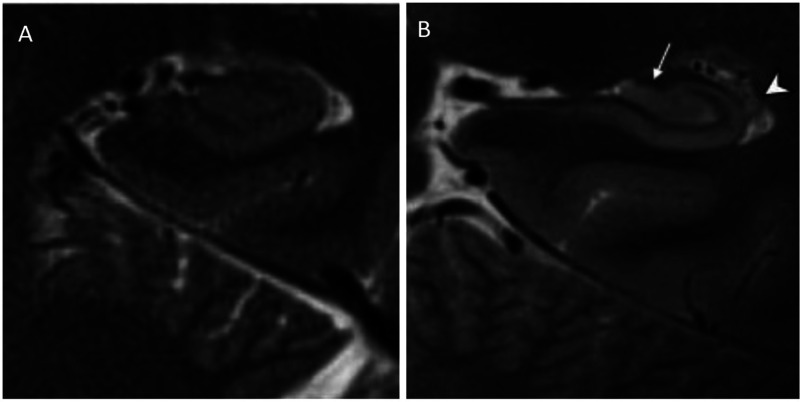

Seven tesla magnetic resonance imaging (7T MRI) is known to offer a superior spatial resolution and a signal-to-noise ratio relative to any other non-invasive imaging technique and provides the possibility for neuroimaging researchers to observe disease-related structural changes, which were previously only apparent on post-mortem tissue analyses. Alzheimer's disease is a natural and widely used subject for this technology since the 7T MRI allows for the anticipation of disease progression, the evaluation of secondary prevention measures thought to modify the disease trajectory, and the identification of surrogate markers for treatment outcome. In this editorial, we discuss the various neuroimaging biomarkers for Alzheimer's disease that have been studied using 7T MRI, which include morphological alterations, molecular characterization of cerebral T2*-weighted hypointensities, the evaluation of cerebral microbleeds and microinfarcts, biochemical changes studied with MR spectroscopy, as well as some other approaches. Finally, we discuss the limitations of the 7T MRI regarding imaging Alzheimer's disease and we provide our outlook for the future.